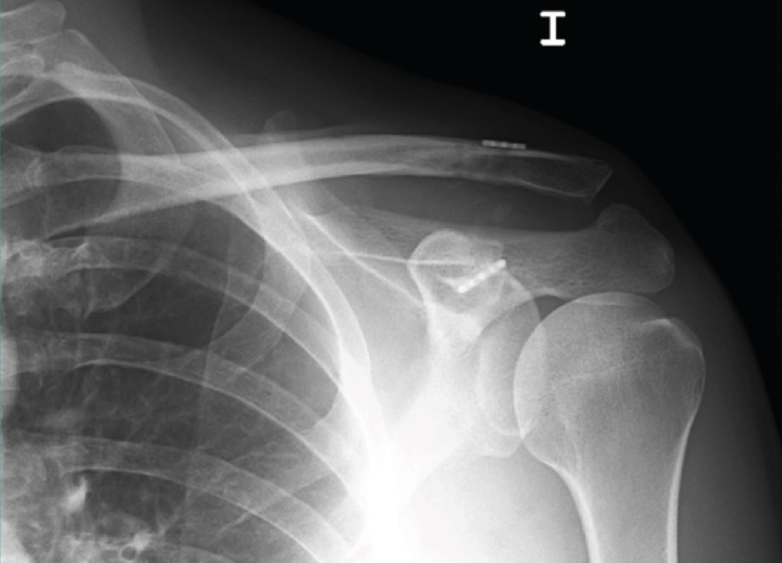

Figura 2. Inserción de las agujas-guía en el extremo clavicular al comienzo de la intervención en que los relieves óseos son fácilmente apreciables. Hombro derecho.

La técnica artroscópica empleada fue la denominada de cerclaje de suspensión cortical coracoclavicular(2). Por encontrarnos más habituados, empleamos la posición de decúbito lateral y los portales de artroscopia posterior, anterolateral y 2 portales anteriores realizados para abordar el espacio subcoracoideo bajo visión directa, según la técnica descrita(5,6,7). En los 6 primeros casos empleamos el dispositivo AC TightRope® (Arthrex, Inc., Naples, Florida). A pesar de su analogía, pero motivado por el cambio de diseño realizado en dicho dispositivo y por el menor orificio requerido, en los 16 restantes casos hemos utilizado el dispositivo AC EndoButton TwinBrigde® (Smith & Nephew, London, England). En los casos con lesiones acompañantes, se emplearon los dispositivos OsteoRaptor 2,3® (Smith & Nephew, London, England) para la reconstrucción de las lesiones de tipo SLAP y el dispositivo TwinFix PK 5,5® (Smith & Nephew, London, England) para el tratamiento de las lesiones de los tendones del manguito rotador. En los últimos 6 casos hemos desestimado el empleo de las guías diseñadas para la implantación de estos dispositivos. Encontramos que su empleo es engorroso, dificulta la selección de los puntos de realización de los túneles óseos y prolonga el tiempo quirúrgico. Optamos por la inserción de las agujas-guía en el extremo clavicular al comienzo de la intervención (Figura 2). En este momento los relieves óseos son fácilmente apreciables. La selección del punto en el cuello de la coracoides se realiza de forma percutánea bajo visión directa (Figura 3). Tras realizar los túneles óseos por taladrado sobre las agujas-guía en la forma habitual, estos se conectan mediante un hilo Vicryl® n.º 2 (Ethicon Endo-Surgery Inc., Cincinnati, Ohio, United States) que hace de pasador final del dispositivo elegido (Figura 4). Si es necesario, se completa la reparación de la fascia trapeciodeltoidea y/o de la cápsula acromioclavicular superior a través del miniabordaje superior asociado.